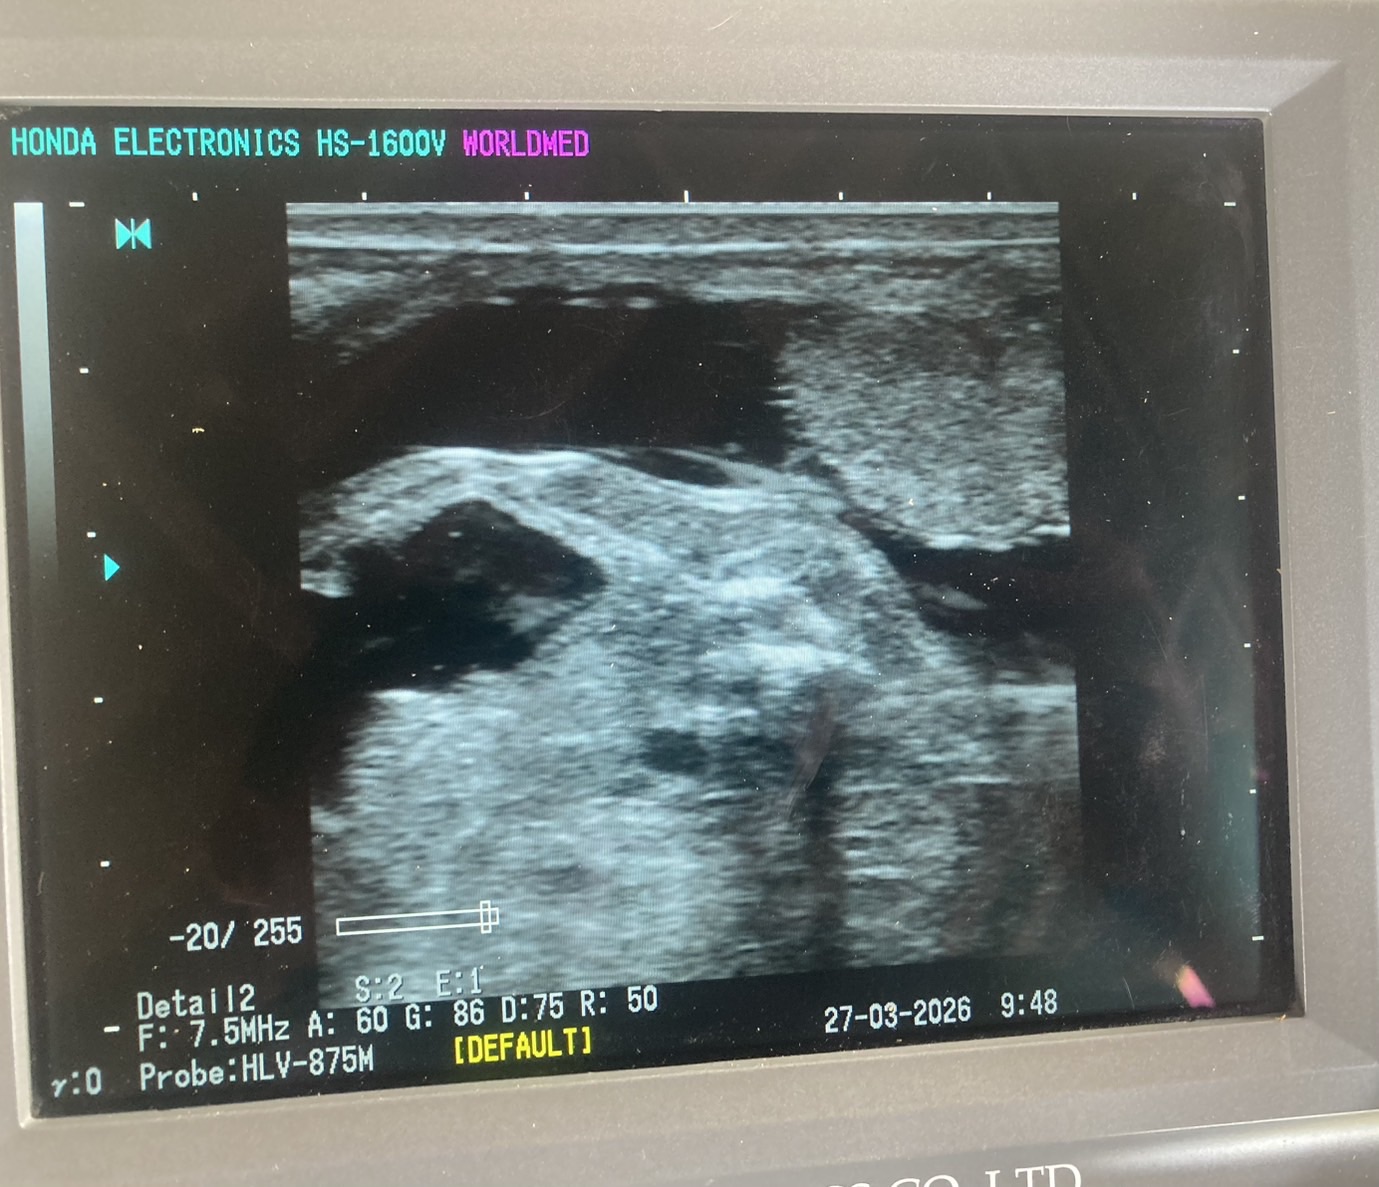

ตรวจท้อง จำนวน 3 ตัว ท้องจำนวน 3 ตัว